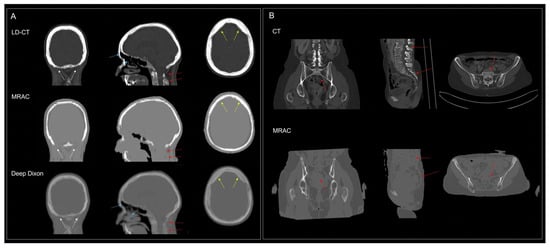

First Clinical Experiences with the Ultra-Fast Time-of-Flight BIOGRAPH One Next-Generation Hybrid PET/MRI System

by Otto M. Henriksen, Kirsten Korsholm, Annika Loft, Johanna M. Hall, Annika R. Langkilde, Vibeke A. Larsen, Thomas S. Kristensen, Caroline Ewertsen, Frederikke E. Høi-Hansen, Patrick M. Lehmann, Karen Kettless, Flemming L. Andersen, Thomas L. Andersen and Ian Law

Diagnostics 2026, 16(3), 398; https://doi.org/10.3390/diagnostics16030398 - 27 Jan 2026

Objective: We present the first clinical experience with the BIOGRAPH One next-generation PET/MRI system scanner, evaluating its performance for body and brain imaging in patients across multiple tracers. Methods: A total of 59 patients were scanned on the BIOGRAPH One PET/MRI following standard clinical PET/CT (n = 52) or first-generation PET/MRI (Biograph mMR, n = 7). Scans comprised 30 total body (TB), whole body (WB), or regional scans with [18F]FDG, and 29 brain scans with either [18F]FDG (n = 5), [18F]FE-PE2I (n = 10), [18F]FET (n = 4), or [68Ga]Ga-DOTATOC (n = 10). The PET image quality was visually assessed using a 5-point Likert scale (1 = very good to 5 = very bad) and compared with clinical scans acquired on either a current-generation digital PET/CT or a first-generation PET/MRI system, including evaluation of diagnostic concordance. PET quantification and image noise was compared in brain and WB/TB [18F]FDG PET scans. Results: PET image quality was rated as good or very good in 93% of scans with a median [inter-quartile range] score of 1.5 [1.5;2]. In 99% of cases, image quality was judged equal to or better than the clinical reference scan (median score 3 [2.5;3]). Diagnostic concordance was observed in 99% of readings. Imaging metrics revealed the anticipated regional bias in brain imaging, while no significant bias was observed in body imaging. Image noise was comparable to that observed with digital PET/CT and demonstrated superiority over first-generation PET/MRI despite potential degradation related to isotope decay in BIOGRAPH One PET/MRI acquisitions scans performed at the end of the imaging workflow. Conclusions: Within the study limitations related to sequential imaging, the BIOGRAPH One PET/MRI scanner demonstrated improved PET sensitivity and workflow potential over its first-generation predecessor, which may allow for broader clinical and research applications. Full article